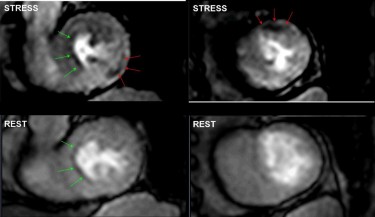

Die Belastung wird durch die Gabe eines vasodilatativen Pharmakons simuliert zB. Hierzu zählt zum Beispiel die Adenosin-Stress-MRT. Sie erlaubt die Darstellung der Durchblutung des Herzmuskels unter pharmakologischer Belastung.

90 - 100 Schlägen pro Minute oder Tachykardien die auf Vorhofflimmern die Herzvorhöfe schlagen nicht mehr regelmäßig sondern vollführen zahlreiche Flimmerbewegungen oder Vorhofflattern. 52 männlich mit Angina pectoris eingeschlossen die wegen des Verdachts auf eine stenosie-rende KHK eine kardiale Adenosin-Stress-Perfusions-MRT inklusive Cine-Ruhe-Funktion Adenosin-Stress- und -Ruhe-Perfusion und Late gadolinium enhancement und. Kombiniert wird die Untersuchung mit einer myokardialen Vitalitätsdiagnostik Late-Enhancement zur Identifizierung infarzierter MyokardbezirkeFibroseEntzündung.

Bei der Untersuchung der Durchblutung der Herzkranzgefässe Stress MRT wird Ihnen über 4 Minuten ein Medikament verabreicht Adenosin das zu. Indikation der DobutaminAdenosin - Stress MRT.